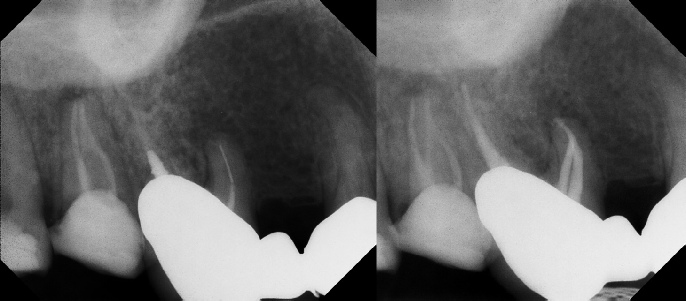

COMPLICATED ANATOMY LARGE LESIONS CALCIFIED CANALS PERFORATION / RESORPTION SEPARATED INSTRUMENTS SURGICAL CASES RETREATMENT / pOST REMOVAL OPEN APICES ACCESS THRU CROWNS Root Canal Case Portfolio

Pre-op Post-op 1 Post-op 2